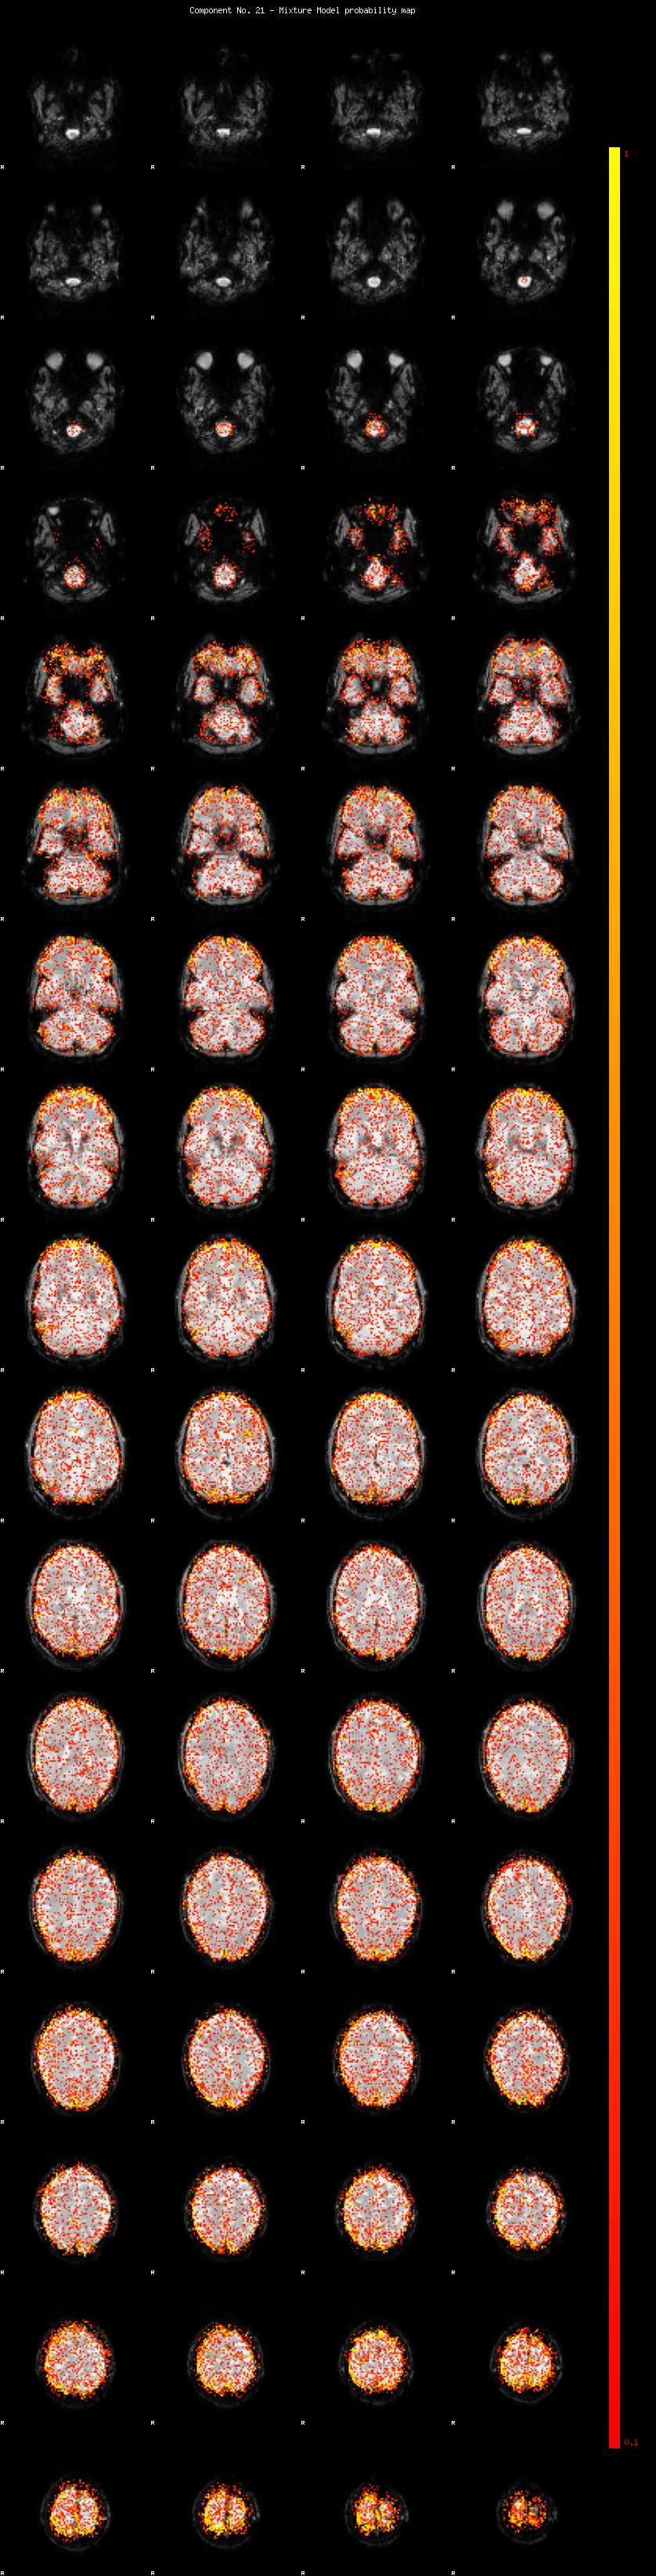

IC_21 Mixture Model fit

Means : 0.000000 2.365380 -2.280119

Vars : 1.000000 1.511392 1.333577

Prop. : 0.890140 0.066636 0.043223